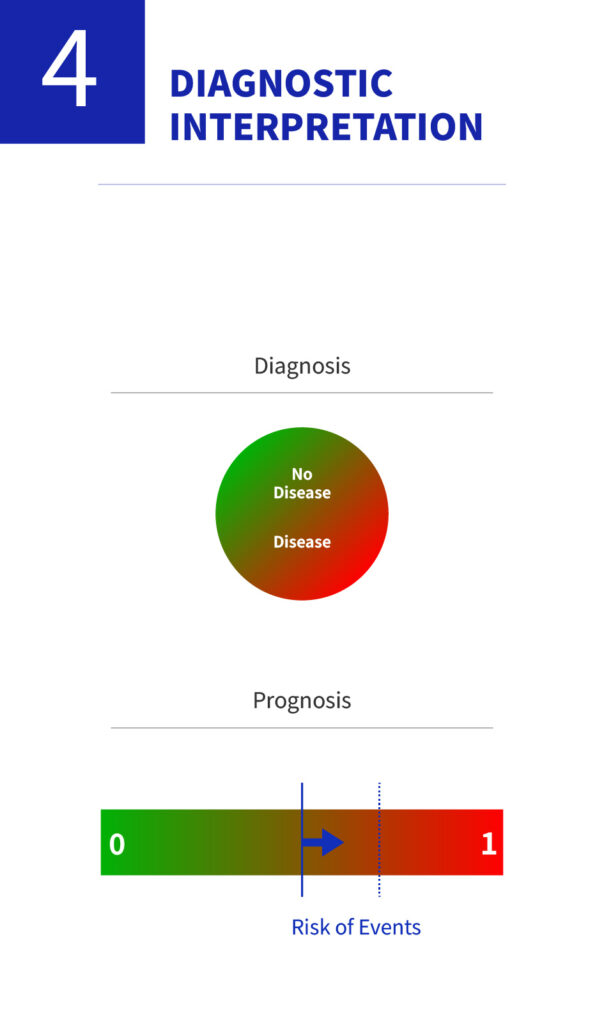

Improving Diagnostic Efficiency and Identifying Disease Associations through AI Technologies

We are enhancing diagnostic accuracy and efficiency by applying AI-based analysis to high-resolution ocular imaging data. By training machine learning models on micro-level features such as leukocyte movement, goblet cell density, and vascular patterns, we aim to uncover associations with various ocular diseases and broader systemic inflammatory or autoimmune conditions.

To support this, we are increasing investments in software and AI infrastructure, with plans to extend our AI diagnostic applications to areas such as systemic disease evaluation and drug response prediction in the near future.